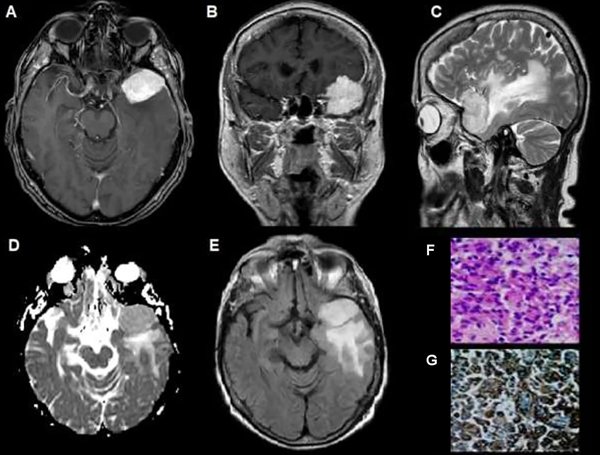

Los 3 grados histológicos (OMS) se categorizaron en 2 grupos: bajo grado (Grado I) y alto grado (Grados II y III) (Figuras 1, 2 y 3).

Figura 1. Meningioma del ala del esfenoides, grado I OMS. (A) RM axial T1 con Gd: lesión con captación hiperintensa y homogénea (flecha). (B) RM axial T1. (C) RM sagital T2: edema perilesional de aspecto hiperintenso (flecha). (D) Mapa de ADC: Comportamiento hiperintenso con aumento de intensidad (flecha). (E) RM FLAIR axial con captación hiperintensa de edema perilesional. (F y G) Microscopía: Proliferación compuesta por células de citoplasma amplio y núcleo redondeado u oval con pseudoinclusiones. Se observa abundante cantidad de vasos dilatados regulares.

Figura 3. Meningioma rabdoide, grado III OMS. (A) RM axial T1: Meningioma temporoocipital derecho con edema perilesional significativo (flecha). (B) RM axial T2: Comportamiento heterogéneo con edema perilesional (flecha).(C) RM coronal T2: comportamiento hiperintenso con abundante edema perilesional. (D) Mapa de ADC:Comportamiento hiperintenso con disminución de intensidad (flecha). (E) RM FLAIR axial: Lesión extensa con abundante edema perilesional, (F y G) Microscopía: Meningioma con amplios sectores de diferenciación rabdoide, presencia de pleomorfismo y atipia nuclear, que alterna con sectores fusocelulares, necrosis y más de 20 mitosis por 10 campos de aumento.